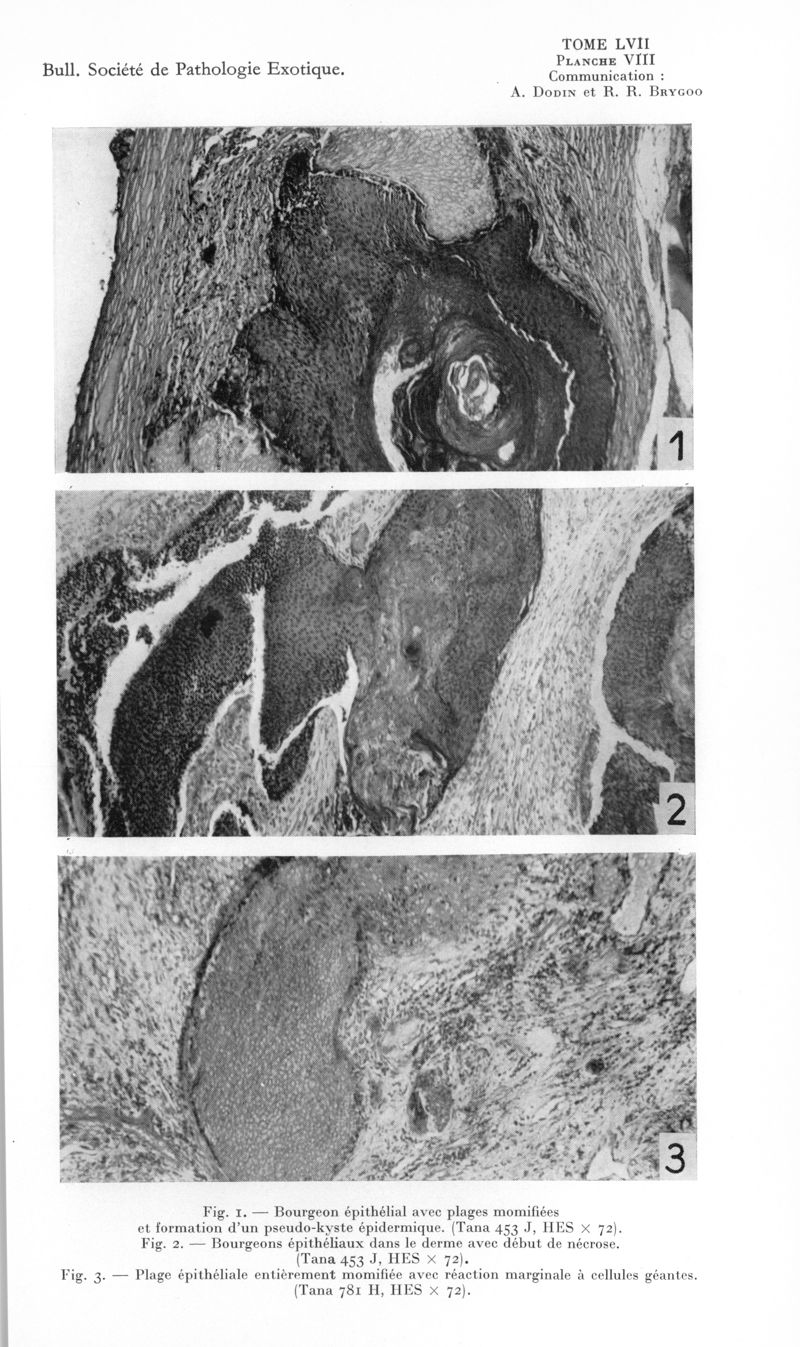

Bulletin de la Société de pathologie exotique et de ses filiales

1964, tome 57. - Paris : Masson, 1964.